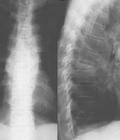

骨关节结核(bone and joint,tuberculosis of)结核菌经呼吸道或消化道侵入人体,形成原发灶,结核菌在原发灶进入淋巴血行播散到全身各脏器,特别是网状内皮系统包括骨关节,多数播散灶被吞噬细胞所消灭,而极少数播散早潜伏下来,一旦人体抵抗力降低,潜伏感染灶中的结核菌繁殖,突破包围的组织而发病。